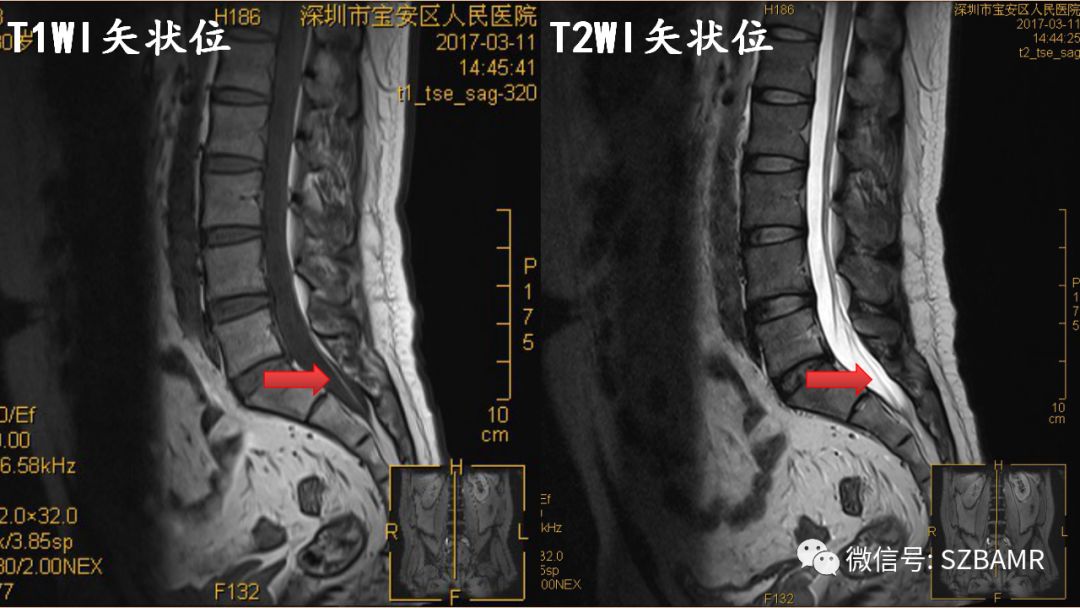

影像表现:矢状位 T1WI是最佳序列,轴位T1WI确定终丝的位置,二者结合可判断终丝脂肪沉积类型,显示脊髓栓系及其他畸形。

Case1:男,54岁,腰痛2月伴右下肢麻木疼痛,加重2天。

T1矢状位见条状高信号,T2矢状位可见起始于脊髓圆锥,T2轴位可见终丝增粗,有高低混杂信号。